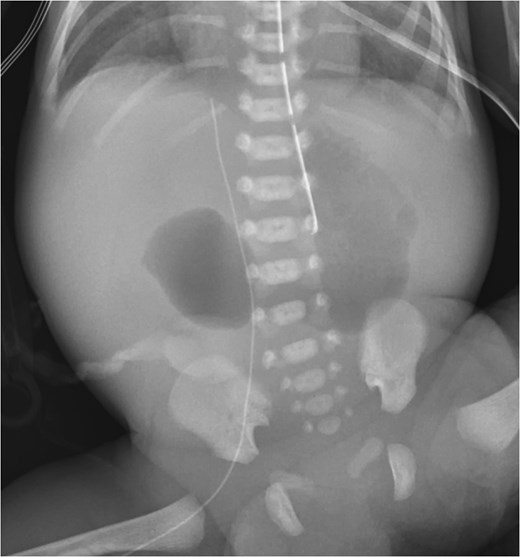

A male was born at 30 weeks via cesarean-section to a 37-year-old mother whose pregnancy was complicated by maternal obesity, polyhydramnios requiring amnioreduction, positive Group B Streptococcus (GBS) screen, and a maternal enterococcal urinary tract infection (UTI) at birth. This patient had appearance, pulse, grimace, activity, and respiration (APGAR) scores of 4 and 7, at 1 and 5 min, respectively. Duodenal atresia was suspected prenatally as a “double bubble” sign had been observed on fetal ultrasound. The diagnosis was confirmed after birth with an abdominal radiograph redemonstrating a double bubble sign (Fig. 1). The patient was admitted to the neonatal intensive care unit (NICU) with a supplemental oxygen requirement and orogastric tube (OGT). On day of life (DOL) two, the patient developed bacteremia with gram positive cocci in pairs and chains. Infectious Disease recommended treating with a 2-week course of ampicillin and gentamicin. The NICU advocated for delaying surgery, so the patient was maintained NPO, receiving total parenteral nutrition (TPN) with lipids via a peripherally inserted central catheter (PICC) line. On DOL seven, blood cultures were negative, the patient weighted 1300 g, and was determined ready for surgery.